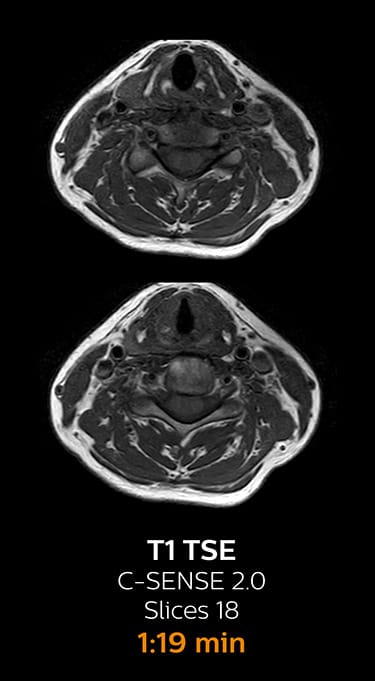

Fast MRI of lumbar spine

With Compressed SENSE, the scan time for the routine lumbar spine examination at KNC was reduced from 11:41 to 8:17 minutes,

which corresponds to 34% reduction.

MRI examination of lumbar spine with Compressed SENSE

MRI examination of the lumbar spine with Compressed SENSE

Ingenia 3.0T CX

Scan time 8:17 min. (was 11:41 min. without Compressed SENSE)